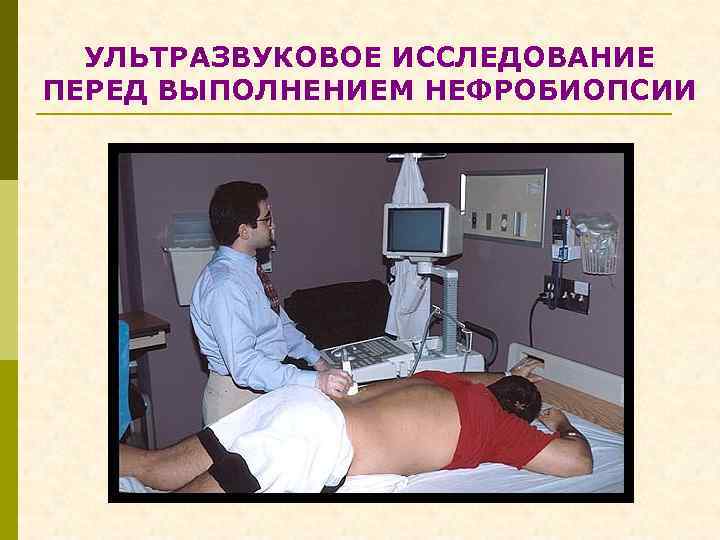

УЛЬТРАЗВУКОВОЕ ИССЛЕДОВАНИЕ ПЕРЕД ВЫПОЛНЕНИЕМ НЕФРОБИОПСИИ